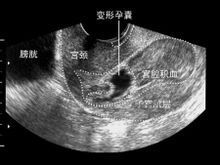

孕囊不規則

孕囊只在懷孕早期見到。孕囊形態不規則,多是流產先兆;孕囊形態異常或位置下移,多是預後不良。

孕囊不規則孕囊只在懷孕早期見到。它的大小,在孕1.5個月時直徑約2厘米,2.5個月時約5厘米為正常。孕囊位置在子宮的宮底、前壁、後壁、上部、中部都屬正常;形態圓形、橢圓形、清晰為正常;如孕囊為不規則形、模糊,且位置在下部,孕婦同時有腹痛或陰道流血時,可能要流產。原因